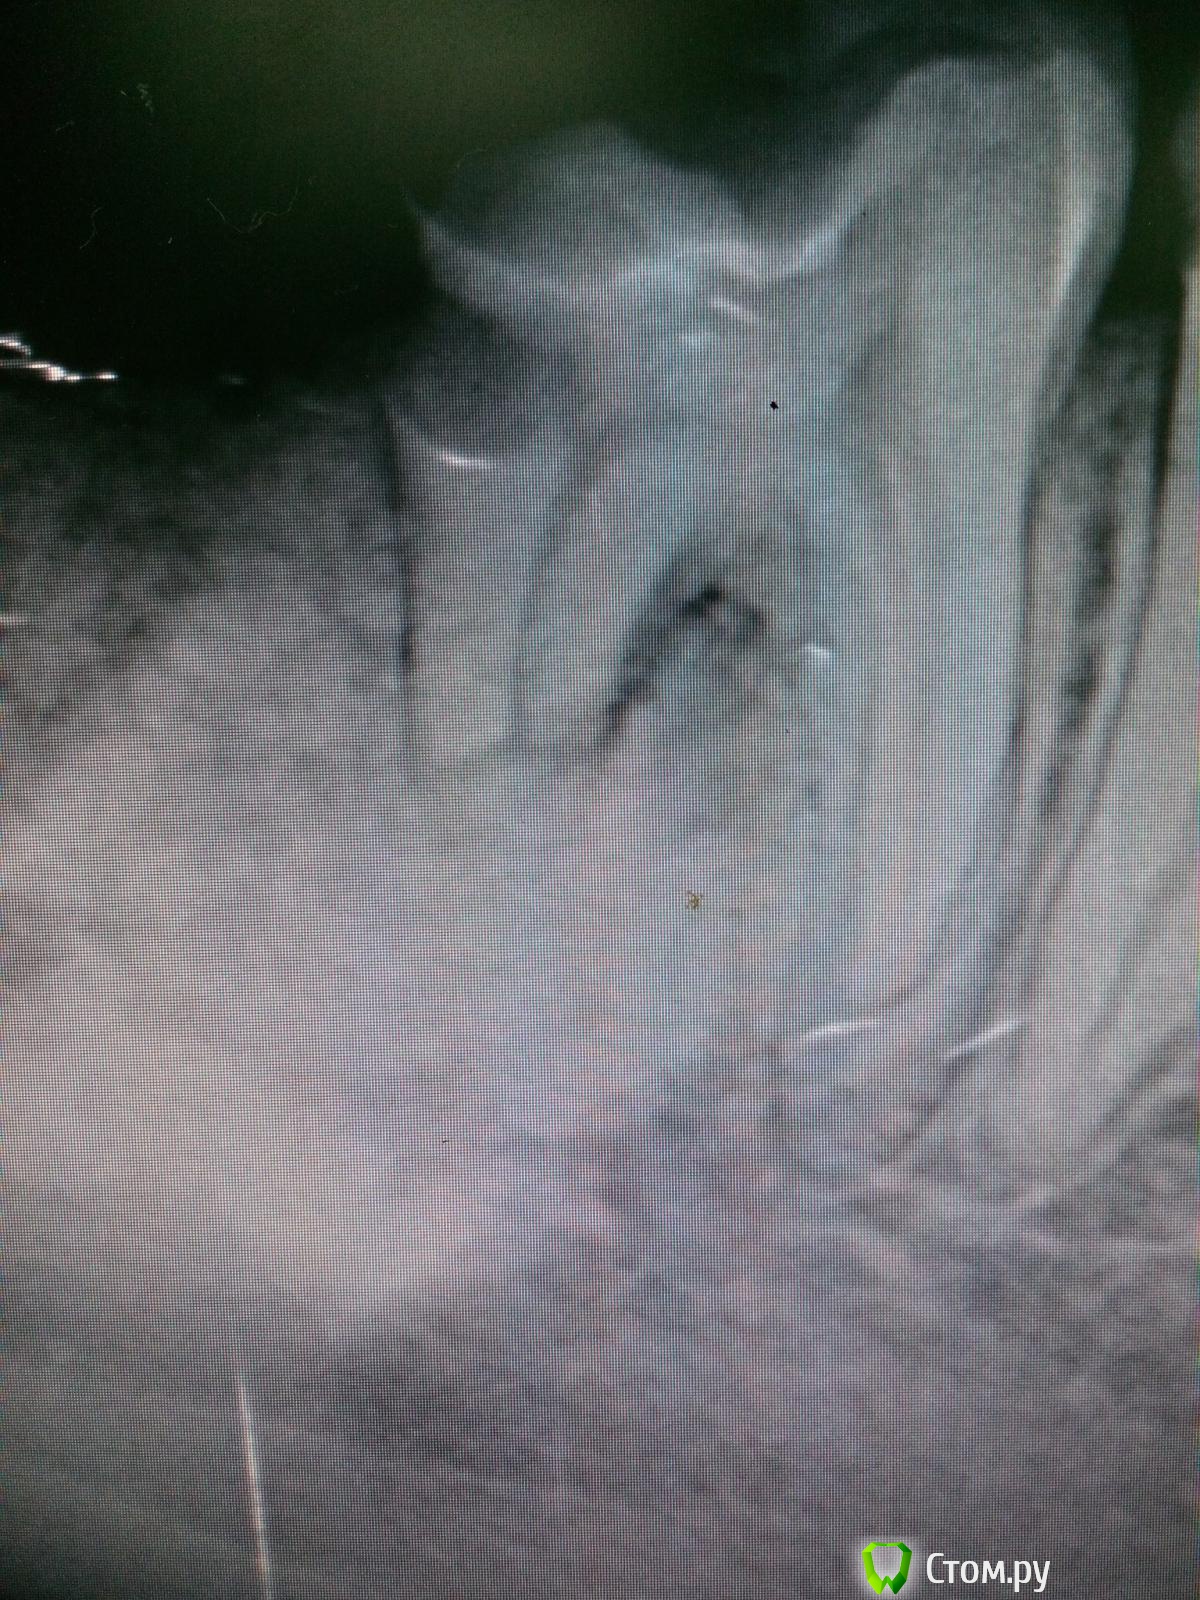

Бардо Опубликовано 25 сентября, 2014 Поделиться Опубликовано 25 сентября, 2014 (изменено) Сегодня пришел парень из местной ЧЛХ, 26 лет, куда его отправил другой терапевт. Жалобы на боли при накусывании, перкуссия положительная. Из доп методов только этот вот прицельный снимок. В бумажке от хирурга значилось: "Диагноз 'остеома', запломбировать 'до верхушки', повторная РГ через полгода" Собственно, какие мнения? Пломбировать 'до верхушки' что-то совсем не хочется. Изменено 25 сентября, 2014 пользователем Бардо Ссылка на комментарий